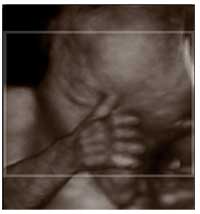

Ao longo dos anos, as coisas mudaram. A tecnologia avançou e, de certa forma, acabou com o mistério da gestação. A ultrassonografia, cada vez mais clara e limpa, começou a mostrar o sexo da criança, uma descoberta que, antes, só se fazia no nascimento.

Com o avanço, a questão da recordação mudou. E, pelo menos fora do Brasil, empresas começaram a oferecer aos pais filmes ~ feitos através do processo de ultrassonografia ~ de seus filhos ainda no útero. É como se fosse uma lembrança antes da vida ou, pelo menos, do nascimento.

Interessante, não? Afinal, você poderá mostrar ao seu filho ou filha como ele era antes do nascimento. Inaugurou-se, assim, um novo mercado. E uma nova forma de recordação, um mercado, pelas informações da BBC Brasil, em franca expansão.

Só que as autoridades medicas estão recomendando que as mães não façam isso. Só devem se submeter à ultrassonografia se ela for necessária e recomendada pelos médicos que acompanham a gravidez.

O que temem? Que o feto seja afetado. Existem provas que isso ocorra? Ainda não. Mas fica a recomendação de se evitar um processo que, de alguma forma, pode ser prejudicial à criança que ainda não nasceu.